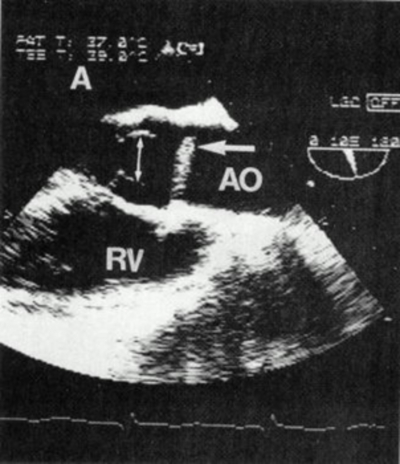

Left Ventricular Outflow Tract Obstruction

Left ventricular outflow tract (LVOT) obstruction with or without systolic anterior motion (SAM) of the mitral valve can also result in hypotension (Figure 8).

Figure 8 – Systolic anterior motion of the mitral valve (MV) and mitral-septal contact causing left venticular (LV) outflow tract obstruction. This condition may cause severe hypotension, especially in hypovolemic patients with hypertrophic cardiomyopathy. Hypotensive patients with SAM can be treated with volume and beta blockers which reduce systolic anterior motion and obstruction by decreasing early left ventricular ejection acceleration, decreasing the early systolic pushing force on the protruding mitral leaflet. From Wigle ED, Sasson Z, Henderson MA, et al. Hypertrophic cardiomyopathy. The importance of the site and extent of hypertrophy. A review. Prog Cardiovasc Dis 1985;28:1-83.

Patients with hypertrophic obstructive cardiomyopathy (HOCM) or subvalvular aortic stenosis, are at particular risk for cardiovascular collapse during traumatic injury. This cardiac lesion is made worse with tachycardia and low cardiac filling pressures. Restoring intravascular volume together with avoiding tachycardia are key in resuscitating these patients. TEE can help establish the diagnosis, but it can also aid in management of heart rate since there is hesitancy to use beta blocking drugs in hypotensive trauma patients. ICU management of HOCM patients will also be streamlined if the diagnosis is made early in the admission.